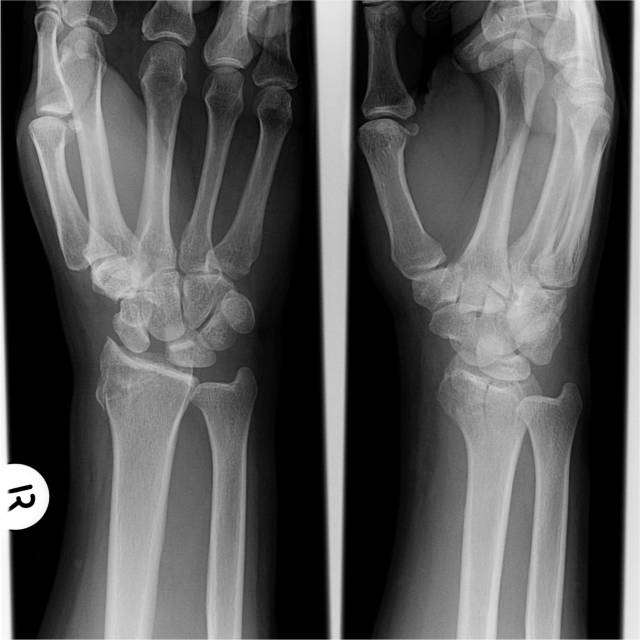

发生在腕关节的“稀疏牙缝征”

影像表现:当舟月骨分离、舟月骨间韧带撕裂所致腕关节正位片或CT冠状位示舟月骨间隙增宽,形似稀疏的牙缝。

征象解析:舟月骨分离是腕关节不稳定最常见的类型,又称为腕舟骨旋转半脱位,多由作用于腕关节尺掌侧的背伸、尺偏和旋后暴力引起稳定舟骨近极的韧带断裂,导致舟月骨间分离。同时桡侧副韧带和桡舟头韧带也可断裂。

影像学检查:X线片(进行双侧比较):

(1)舟月骨间间隙>2mm为可疑分离,如>4mm即可诊断。

(2)皮质环征,环下界与舟骨近极关节面的间距<7mm。

(3)舟骨缩短。

(4)舟月角>70º;桡月角>20º,即DISI。